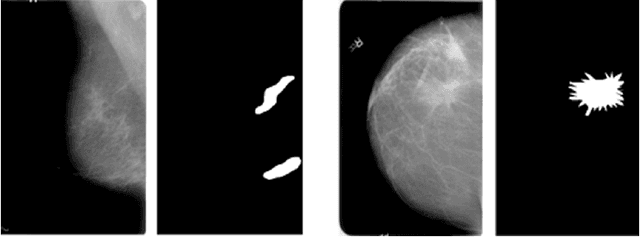

Abstract:The study introduces an integrated framework combining Convolutional Neural Networks (CNNs) and Explainable Artificial Intelligence (XAI) for the enhanced diagnosis of breast cancer using the CBIS-DDSM dataset. Utilizing a fine-tuned ResNet50 architecture, our investigation not only provides effective differentiation of mammographic images into benign and malignant categories but also addresses the opaque "black-box" nature of deep learning models by employing XAI methodologies, namely Grad-CAM, LIME, and SHAP, to interpret CNN decision-making processes for healthcare professionals. Our methodology encompasses an elaborate data preprocessing pipeline and advanced data augmentation techniques to counteract dataset limitations, and transfer learning using pre-trained networks, such as VGG-16, DenseNet and ResNet was employed. A focal point of our study is the evaluation of XAI's effectiveness in interpreting model predictions, highlighted by utilising the Hausdorff measure to assess the alignment between AI-generated explanations and expert annotations quantitatively. This approach plays a critical role for XAI in promoting trustworthiness and ethical fairness in AI-assisted diagnostics. The findings from our research illustrate the effective collaboration between CNNs and XAI in advancing diagnostic methods for breast cancer, thereby facilitating a more seamless integration of advanced AI technologies within clinical settings. By enhancing the interpretability of AI-driven decisions, this work lays the groundwork for improved collaboration between AI systems and medical practitioners, ultimately enriching patient care. Furthermore, the implications of our research extend well beyond the current methodologies, advocating for subsequent inquiries into the integration of multimodal data and the refinement of AI explanations to satisfy the needs of clinical practice.